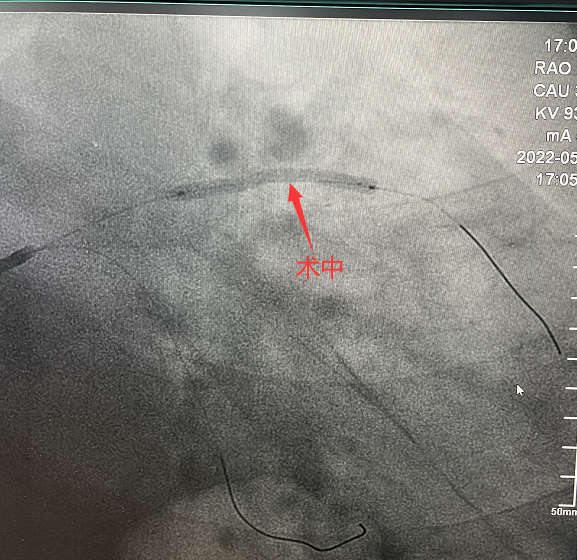

可吸收支架植入手術(shù)中

手術(shù)造影圖